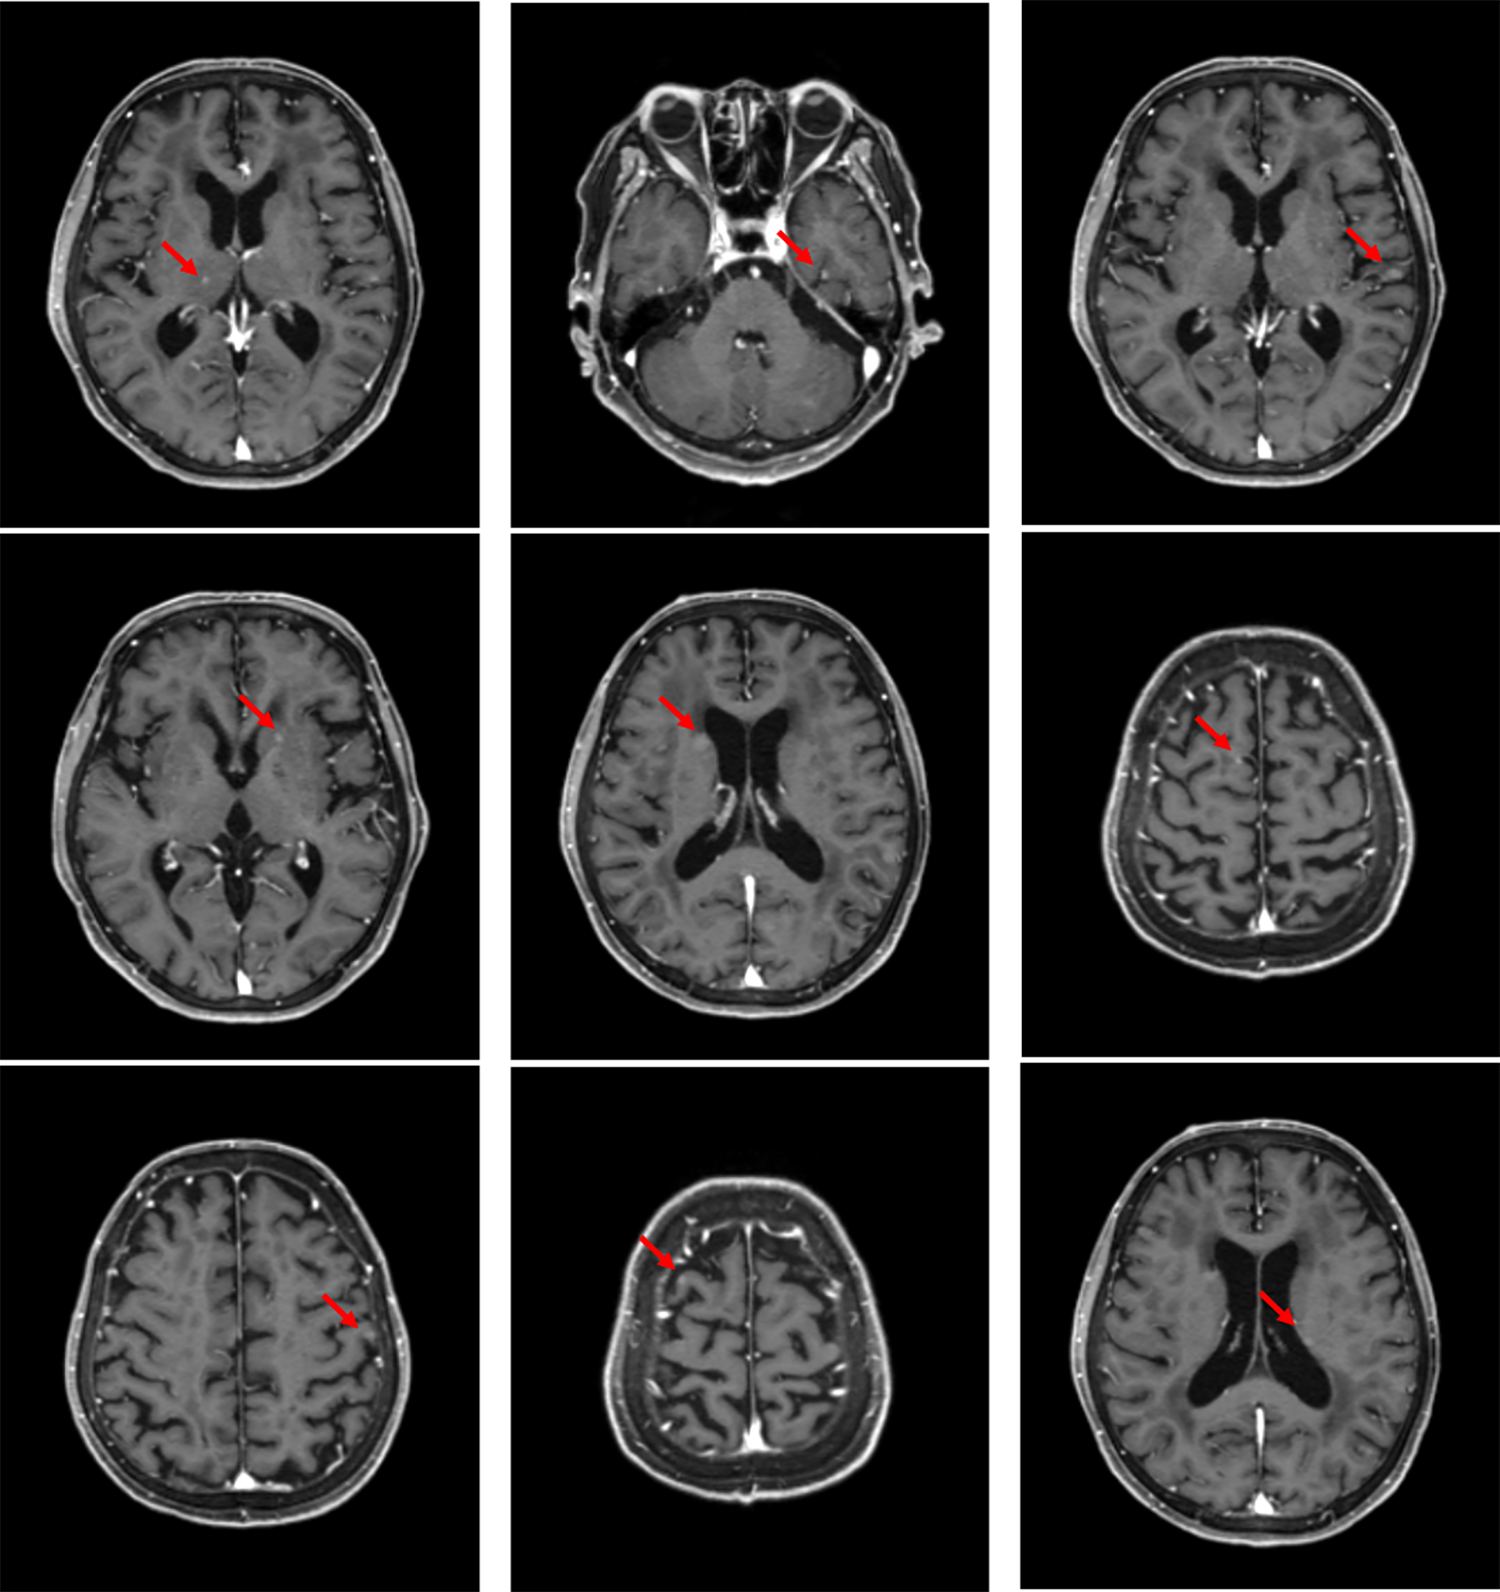

ガドビストを用いた転移性脳腫瘍の検出

右下葉肺腺癌cT4N0M1c StageⅣBの診断となり、化学療法を行う方針となった。

造影MRIは脳転移の検出において最も感度が高い検査であり、非侵襲的に微小な脳転移も描出可能とされる。脳転移の有無、数、場所が明確になることで予後の予測や治療方針の決定に寄与する。他の病変(原発性脳腫瘍、脳膿瘍など)との鑑別や治療効果の判定、経過観察にも有用である。治療後の画像で再発と壊死の鑑別が難しい場合があり、PETやMRSなどの追加検査が必要な場合がある。また、ガドリニウム造影アレルギーの既往のある患者は禁忌であり、重篤な腎障害機能障害のある患者は電子添文での警告に該当する。

本症例ではガドビスト投与による造影MRIで微小な脳転移を検出することが可能だった。